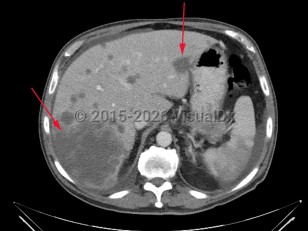

Liver cancer refers to a malignancy that arises primarily within the liver. There are several types of liver cancers. Hepatocellular carcinoma, accounting for approximately 75% of primary liver cancers, is due to malignant transformation in hepatocytes. This is most commonly seen in patients with cirrhosis of any etiology (eg, chronic viral hepatitis, alcohol-related liver disease, nonalcoholic steatohepatitis). Cholangiocarcinoma is the second most common primary liver cancer, accounting for approximately 10%-20% of cases. This is a cancer of bile duct origin.

Many malignancies can metastasize to the liver. Frequently, patients with uveal melanoma may have liver metastases. In rare circumstances, lymphomas can present with primary manifestation in the liver.